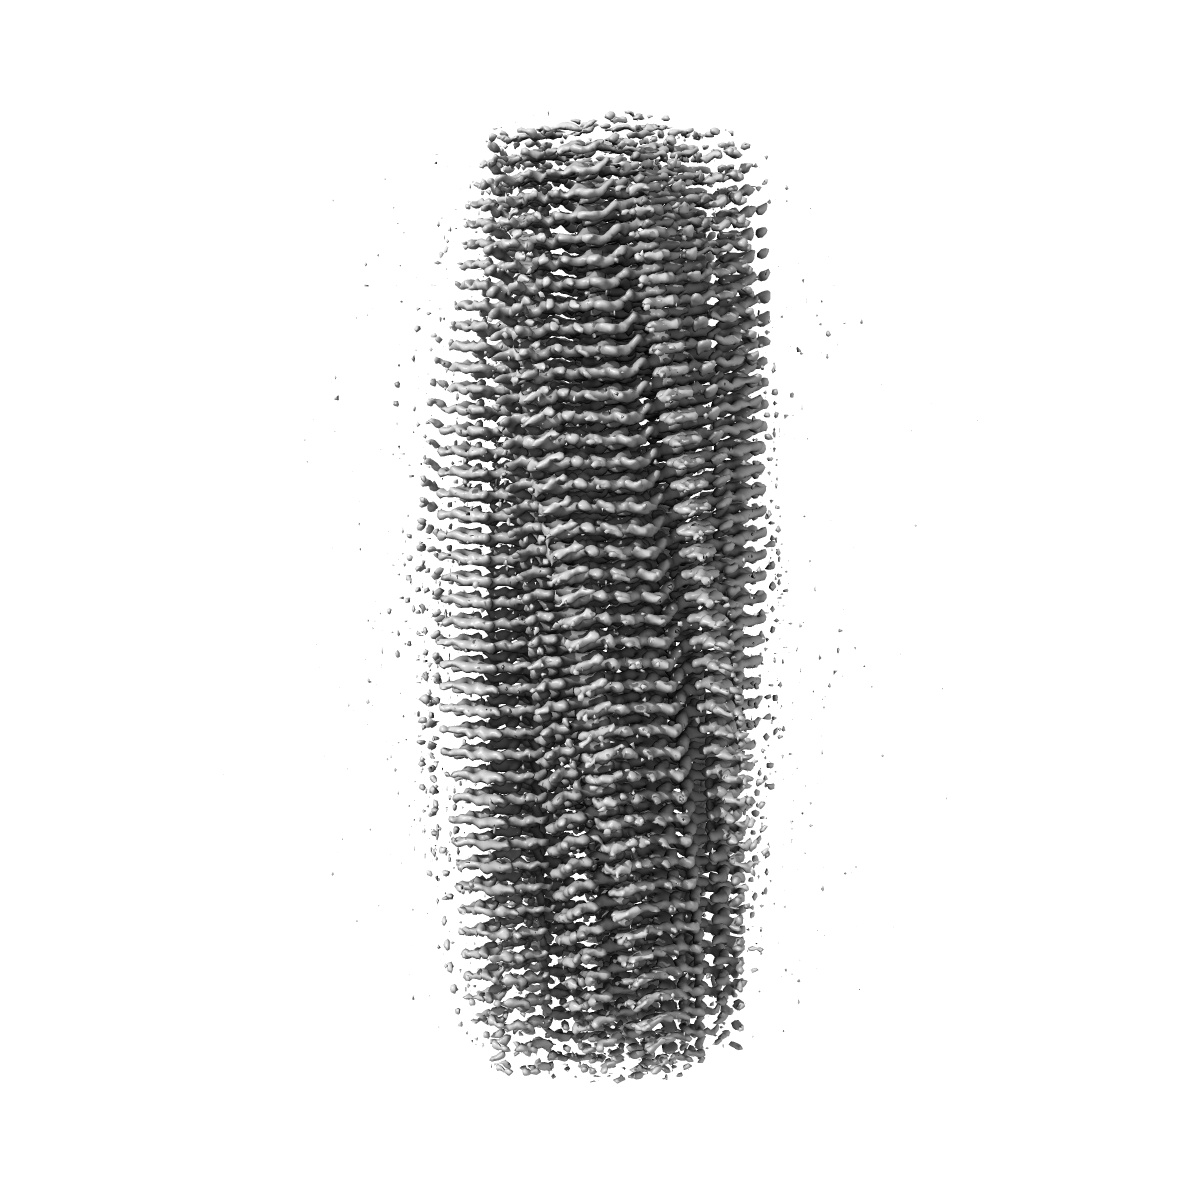

Structure of heteromeric amyloid filament of TDP-43 and AXNA11 from FTLD-TDP Type C (variant 2)

Helical reconstruction2.9 Å

Sample: heteromeric amyloid filament of TDP-43 and AXNA11 from FTLD-TDP Type C (variant 1)

Heteromeric amyloid filaments of ANXA11 and TDP-43 in FTLD-TDP Type C.

- Arseni D, Nonaka T, Jacobsen MH, Murzin AG, Cracco L, Peak-Chew SY, Garringer HJ, Kawakami I, Suzuki H, Onaya M, Saito Y, Murayama S, Geula C, Vidal R, Newell KL, Mesulam M, Ghetti B, Hasegawa M & Ryskeldi-Falcon B. (2024) Heteromeric amyloid filaments of ANXA11 and TDP-43 in FTLD-TDP Type C. Nature,